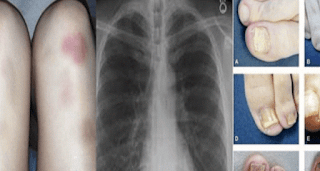

OBRATITE PAŽNJU: OVO SU NAJRANIJI ZNAKOVI DA RAK RASTE U VAŠEM TIJELU

Jedan od vodećih uzroka smrti je itekako rak. Naravno, kao i svaka bolest, što se prije uoči imamo više mogučnosti da se izliječimo. Kao i za svaku bolest tijelo daje itekakve signale. Kada je riječ o tumoru, nemojte gledati samo rutinske testove, nego poslušajte malo i svoje tijelo šta vam govori.

Upravo iz tog razloga smo odlučili podijeliti sa vama par znakova koje vma tijelo šalje i traži pomoć:

Šištanje ili teško disanje

Pojava masnica ili često krvarenje iz nosa

Slabost i umor

Hronični kašalj ili bol u grudima

Neprestana temperatura ili infekcija

Iznenadni vrlo bolni mentsrualni ciklusi ili krvarenje između ciklusa

Problemi sa gutanjem

Otečeni limfni čvorovi ili grudvice na vratu, ispod pazuha ili prepona

Nadutost ili dobijanje težine u predjelu abdomena

Osjećaj sitosti i nemogućnost jedenja

2

Rektalno krvarenje ili krv u stolici

Bol u karlici ili stomaku

Neobjašnjiv gubitak kilograma

Uznemiren stomak ili bol u stomaku

Promjene na bradavicama

Crvene, bolne ili otečene dojke

Otok ili promjene na licu

Neprestana upala ili grudvice koje se ne povlače i krvare

Bol u leđima ili sa donje desne strane

Izvor: mojrecept.info